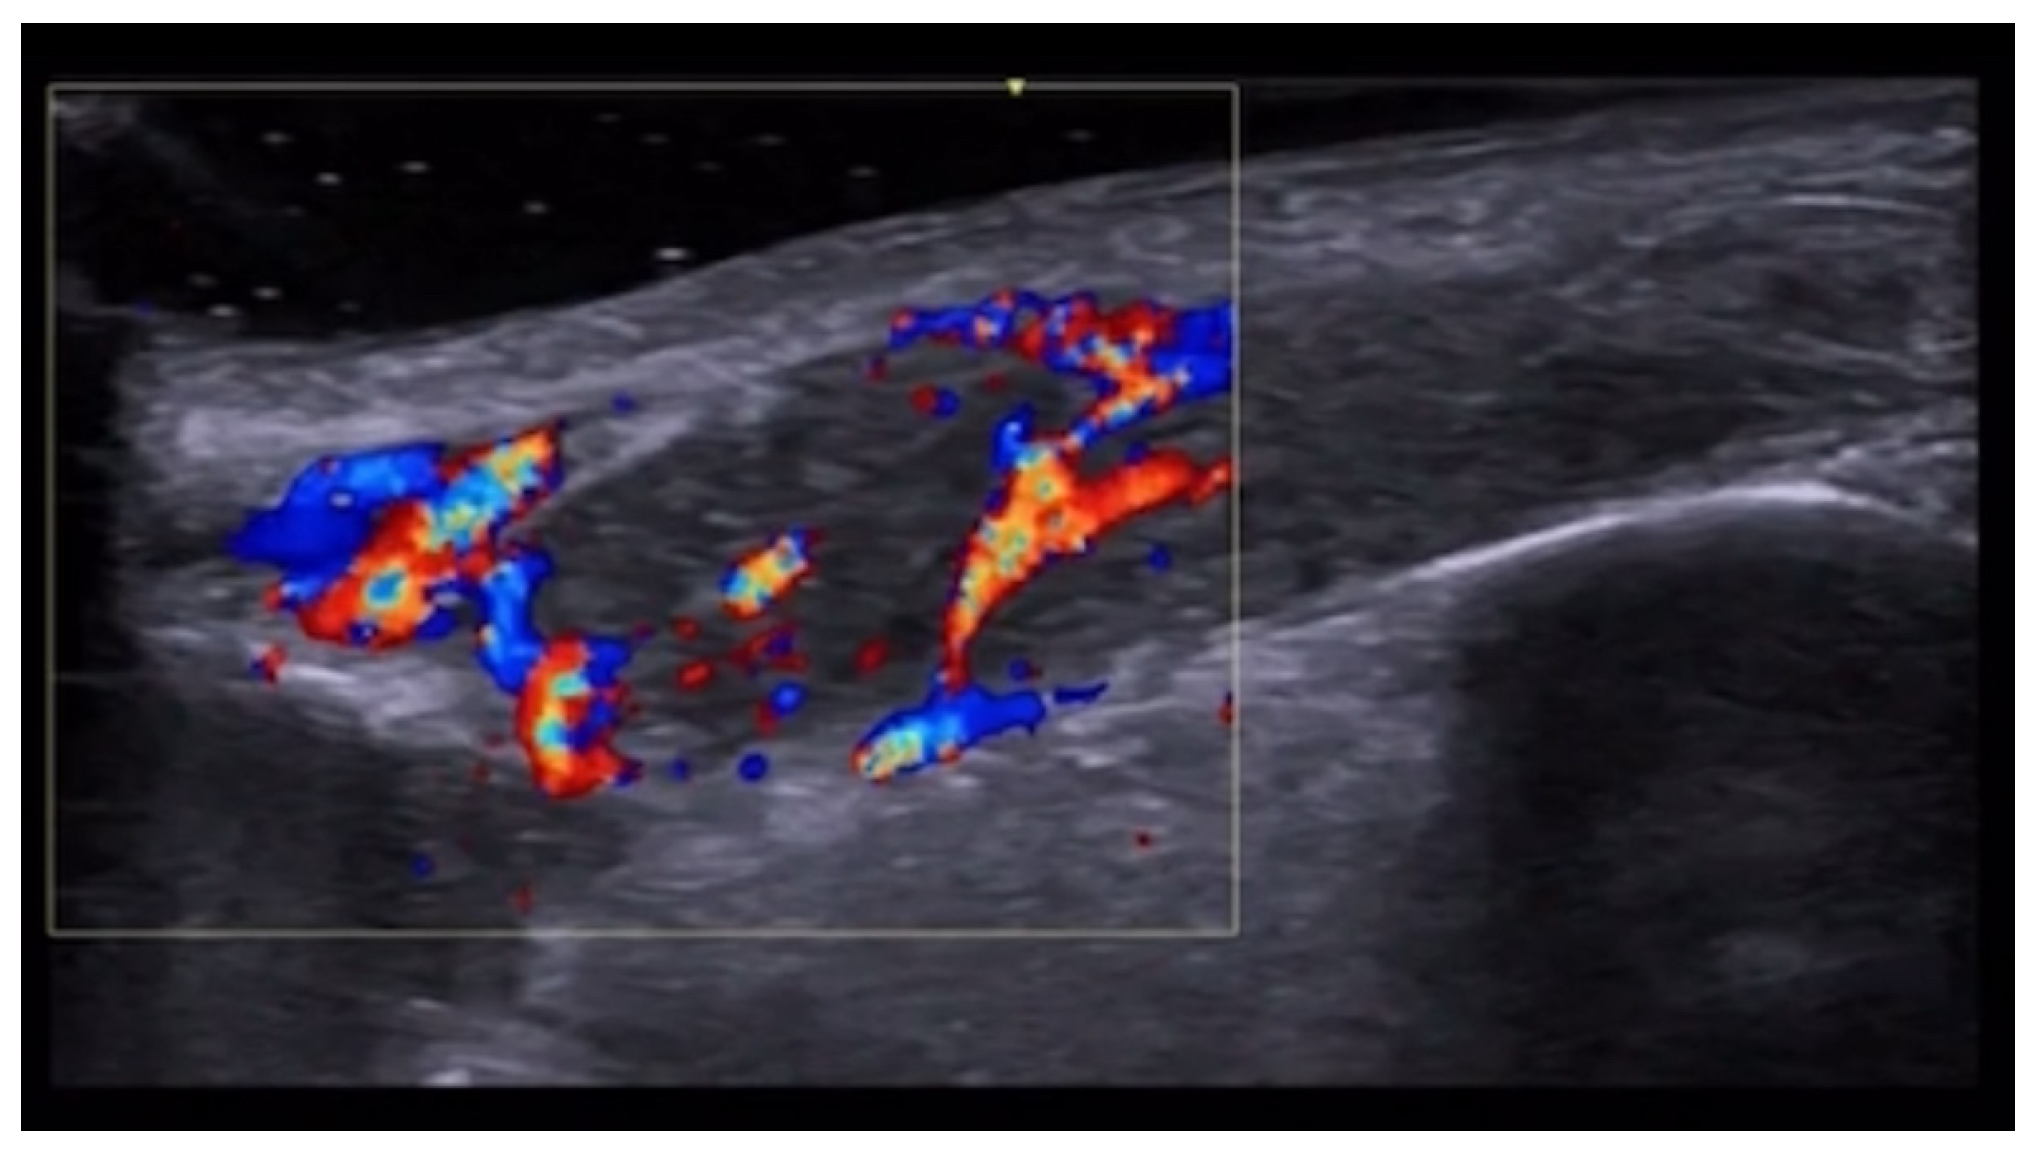

5. Specific Cutaneous Structure and Sites of Skin Disorders

6. Vascular Disorders